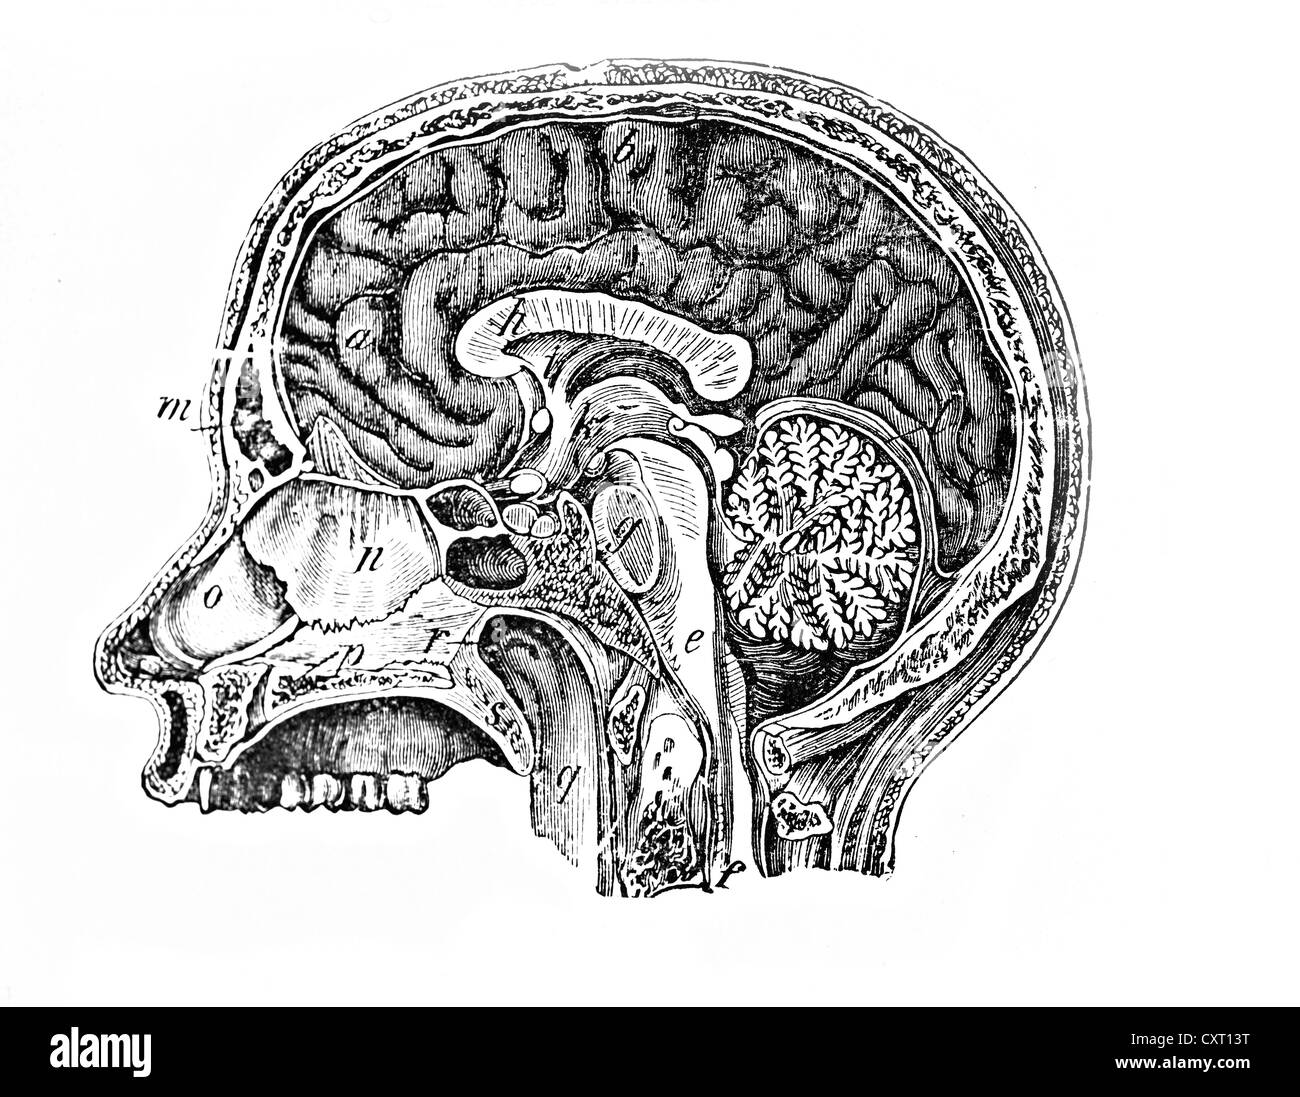

Longitudinal section of a human head, anatomical illustration, 1896, Stock Photohttps://www.alamy.com/image-license-details/?v=1https://www.alamy.com/longitudinal-section-of-a-human-head-anatomical-illustration-1896-image67062958.html

Longitudinal section of a human head, anatomical illustration, 1896, Stock Photohttps://www.alamy.com/image-license-details/?v=1https://www.alamy.com/longitudinal-section-of-a-human-head-anatomical-illustration-1896-image67062958.htmlRMDW2YDJ–Longitudinal section of a human head, anatomical illustration, 1896,

Longitudinal section of a human head, anatomical illustration Stock Photohttps://www.alamy.com/image-license-details/?v=1https://www.alamy.com/stock-photo-longitudinal-section-of-a-human-head-anatomical-illustration-50929532.html

Longitudinal section of a human head, anatomical illustration Stock Photohttps://www.alamy.com/image-license-details/?v=1https://www.alamy.com/stock-photo-longitudinal-section-of-a-human-head-anatomical-illustration-50929532.htmlRMCXT13T–Longitudinal section of a human head, anatomical illustration